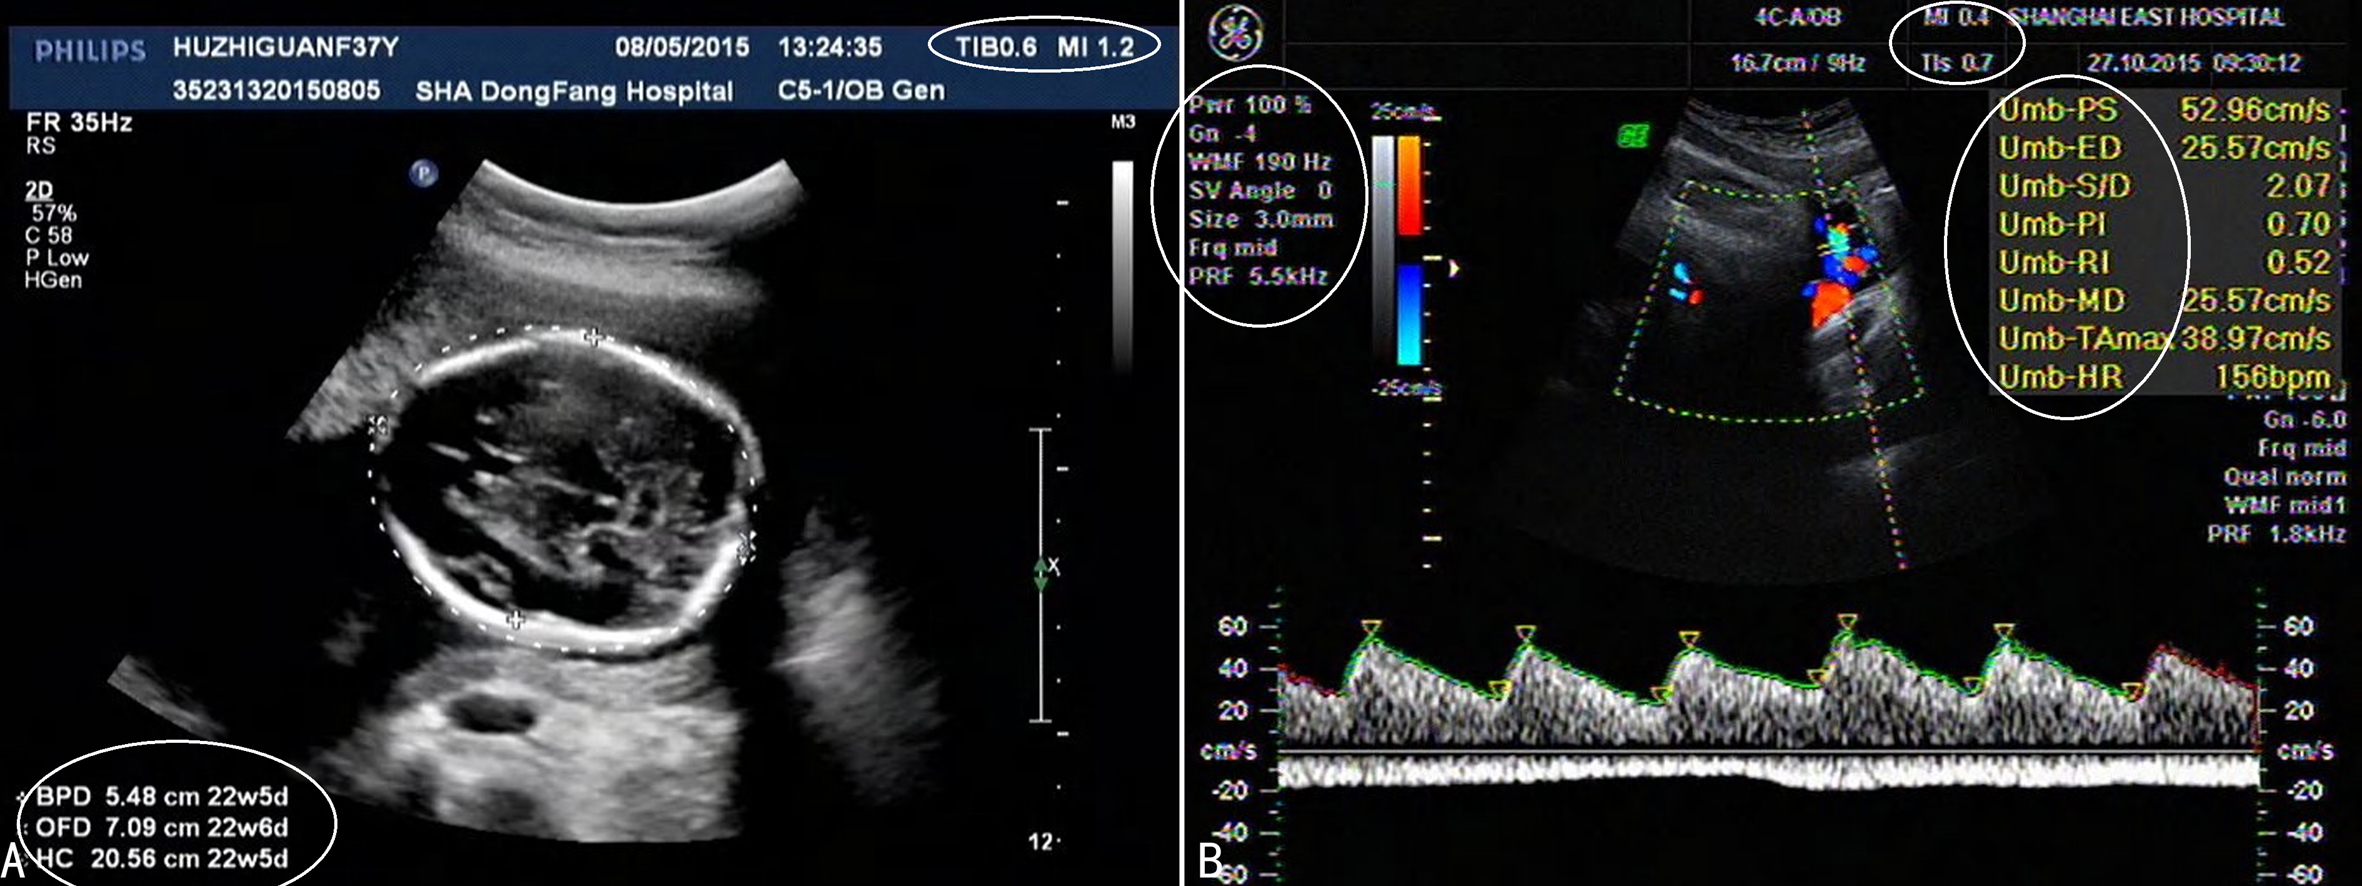

多普勒检查仪器显示仪器可以显示血流速度、脉冲重复频率、多普勒超声频率、机械指数和热指数(图2A);具有最大速度包络功能,测量参数包括收缩期峰值流速、舒张末期流速、平均速度,并可获得搏动指数、阻力指数、收缩期/舒张期流速比值、胎心率等(图2B)。显示多普勒血流速度曲线后通过一定的测量操作仪器即可自动计算并显示相应的参数。

图2产科超声多普勒检查的显示 椭圆圈示的均是产科超声检查常用的参数